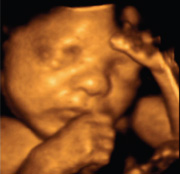

Bei bestimmten Schwangerschaftsrisiken, aber auch auf Ihren Wunsch führen wir einen so genannten „großen“ Organ-Ultraschall durch. Dieser ist nicht mit dem in Ihrem Mutterpass gemäß den Mutterschaftsrichtlinien vorgesehenen Ultraschall-Screening zwischen 19 und 22 SSW gleichzusetzen.

Günstigster Zeitpunkt für die Untersuchung ist die 20.-24. SSW, aber auch spätere Schwangerschaftswochen sind möglich.